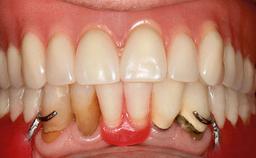

For soft tissue management, the initial healing caps are replaced with a longer type 8 weeks after implant placement in a second intervention before prosthodontic treatment is initiated.

The case concludes with the presentation of the final prostheses at the 3-year follow-up, demonstrating a stable and pleasing soft- and hard-tissue situation.